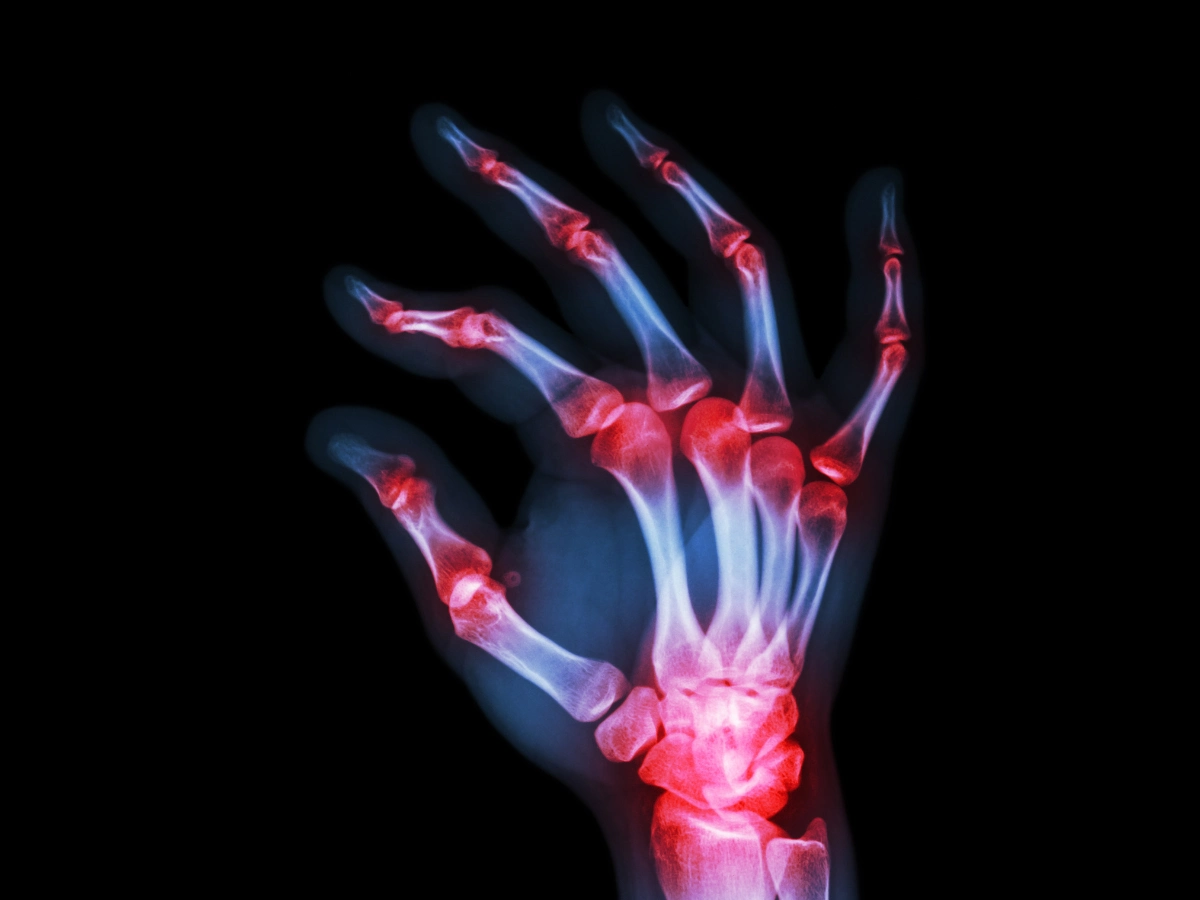

손가락 관절염 치료법

1. 약물치료

주로 증상이 심하지 않은 초기 단계의 경우 생활 습관 교정과 함께 약물로 보존적 치료를 우선적으로 진행하게 됩니다.

일반적으로 퇴행성 관절염의 경우 관절의 염증과 통증을 줄이기 위해 경구용 진통제와 비스테로이드성 항염제를 주로 처방받습니다.

류마티스성 관절염이라면 자가면역질환이기 때문에 여러 가지 약물을 병합해 사용하는 경우가 많습니다.

비스테로이드성 항염제, 경구용 스테로이드, 면역억제제, 생물학적 제제 등이 현재 많이 사용되고 있습니다.

또한 국소적인 염증 및 통증 치료를 위해 먹는 약물 외에 관절 부위에 스테로이드, 줄기세포 약물, 히알루론산을 직접 주사하기도 합니다.

히알루론산은 연골, 관절을 부드럽게 윤활하는 효과가 있으며 완충 역할을 해 관절 통증을 줄여주는 데에 효과가 있기 때문에 많이 사용됩니다.

4. 수술적 치료

손가락 관절염의 진행 정도가 심하여 관절 변형 및 운동 제한이 있고 보존적 치료를 진행했음에도 증상의 개선이 되지 않는 경우 관절 고정술 혹은 인공 관절 수술을 고려해 볼 수 있습니다.

관절의 연골이 모두 닳아 뼈끼리 부딪히게 될 때 통증이 극심해지는데 이때 뼈와 뼈를 이어 붙여 움직이지 않게 만들어 아프지 않게 하는 수술이 관절 고정술입니다.

보통 통증이 제일 심한 부위인 끝마디에 많이 수술합니다. 중간마디는 고정하게 될 경우 불편감이 크기 때문에 이 경우 인공 관절 수술을 많이 선택합니다.

그러나 수술적 치료 방식은 후유증이나 부작용이 발생할 수 있으므로 의료진과 충분히 상담 후 신중하게 결정하는 것을 추천드립니다.